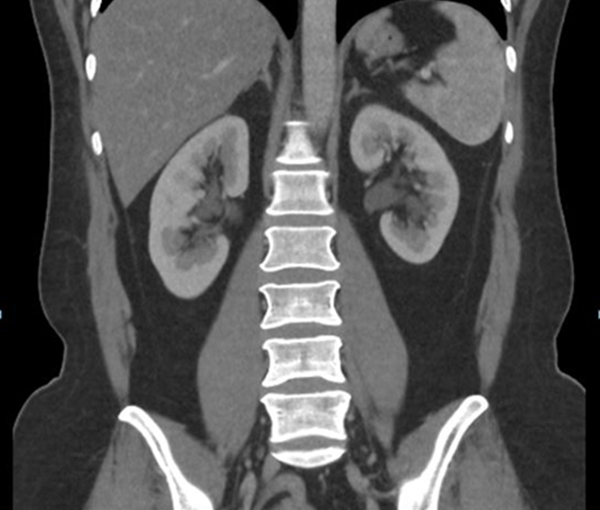

Stage IVA cervical cancer (a) CT scan shows a cervical tumor (black arrow) and an irregular mass that is inseparable from the rectum (white arrow) The latter finding is most consistent with rectal invasion Arrowheads indicate focal urine activity in the right lateral aspect of the uterus caused by uterine displacement of the urinary bladder. HWS und obere Rückenwirbelsäule ?. Le rachis cervical supérieur est défini par les articulations atlas (C1)occiput, atlasaxis (C2) et le disque intervertébral C2C3 Constitué de six articulations synoviales mises en jeu plus particulièrement dans les mouvements de rotations, c’est un site fréquemment atteint au cours des rhumatismes inflammatoires, au premier rang desquelles la polyarthrite rhumatoïde (PR), mais.

Pour répondre au besoin d’inscrire la kinésithérapie dans le modèle de l’evidencebased practice, nous avons soumis les mesures centimétriques de la mobilité des rachis cervical et. Le dispositif comprend une tige (2), un élément occipital (1A) ayant une plaque (11A) à picot (12A) pour être en contact avec et lié à l'occiput (OC), et au moins un élément vertébral (3, 30, 4) ayant une griffe (32, 3) ou une plaque (40) à vis (VC) pour être liée à une vertèbre cervicale (C2 C7) L'élément occipital et l'élément vertébral sont montés sur la tige et. Stage IVA cervical cancer (a) CT scan shows a cervical tumor (black arrow) and an irregular mass that is inseparable from the rectum (white arrow) The latter finding is most consistent with rectal invasion Arrowheads indicate focal urine activity in the right lateral aspect of the uterus caused by uterine displacement of the urinary bladder.